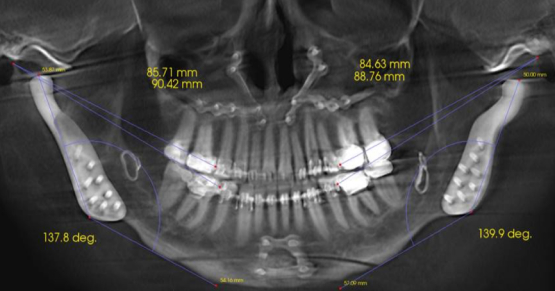

Temporomandibular Joint Space and Articular Disk Position: Is There a Correlation?

Resident Faculty member Dr. Curt Ringhofer explains how early detection of occlusal changes caused by inadequate growth can help lower…By Curt Ringhofer